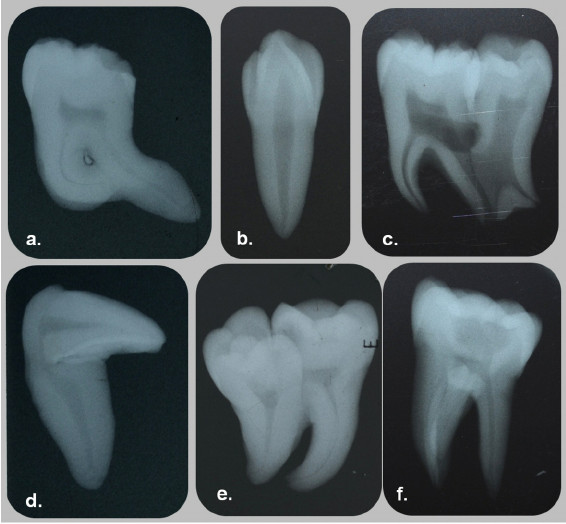

Some form of dental anomalies

Some form of dental anomalies, or at least dental irregularity is found in nearly every individual, including men, women and children. Some of these are relatively mild and simple, as in rotations of teeth, small interdental spacing and unusually shaped teeth. Others are more complex and cause more functional and esthetic concerns. Among the latter, one should include congenitally missing, impacted and severely crowded teeth and also craniofacial anomalies, such as various forms of clefts. An orthodontist, who is primarily concerned with the function and esthetic of the human dentition, sees these dental anomalies as a challenge in his efforts to change a malocclusion to a more normal and cosmetic occlusion.

Second to dental crowding, anomalies in the number of teeth represent a large group of primary factors causing malocclusions. This is closely followed by an anomalous position of teeth, chiefly represented by impactions and ectopic eruption, but also including transpositions and transmigrations. Therefore, these etiologic factors should also be looked at in an effort to understand and reduce or even eliminate them in the future. Consequently, it is necessary to revisit some of the salient features of these anomalies. Particularly challenging will be to summarize the recent investigative reports in this area, as well as to speculate where future research should be directed. Once we are able to substantially reduce these underlying dental anomalies, we will be well equipped and ready to tackle even more complex cranio-facial problems.

It is generally recognized that the most common positional anomaly of a tooth is rotation. Rotations are so prevalent that it is difficult to find a modern man or woman with an occlusion that does not exhibit some degree of this common anomaly. Because this anomaly is so ubiquitous, many clinicians do not even list them as a trait of malocclusion, except when rotations are severe, e.g. a Orthodontics tooth rotated more than 45 degrees.

Ectopic position constitutes the second most common positional anomaly of the dentition. Within this category, the one that concerns clinicians the most is impaction. Even though any one tooth from either dental arch can be impacted, impaction of the maxillary permanent canine receives most attention. This is the case for numerous reasons, including the central role that the canine plays in the function of articulation and occlusion. A second, nearly equally important reason, is its role in facial esthetics.

A brief mention will be made of yet another positional anomaly of the canines: transmigration. Transmigration is exclusive of the mandibular perma- nent canine. In this anomaly, the canine from one side of the arch migrates through the bone and erupts on the opposite side of the arch. For instance, the right mandibular canine migrates through the sympheseal area and erupts into the arch in the place where the left canine usually erupts. This anomaly could present a complex clinical problem, because the clinician will be facing a situation where the canine from one side appears to be missing, while the opposite side may appear to have a supernumerary canine.15 Like so many dental problems, this last anomaly is best detected by radiographic examination. If detected early enough, its treatment may not be too difficult. This will reinforce the urging of a mature teacher to obtain and examine our patients’ records with care and attention to detail.